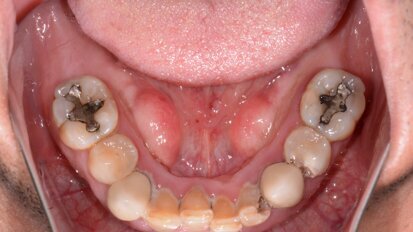

Atraumatic extraction of maxillary first premolar

A 70-year-old female patient visited our clinic owing to a fractured maxillary first molar. Tooth #24 had previously had a large composite restoration that ...